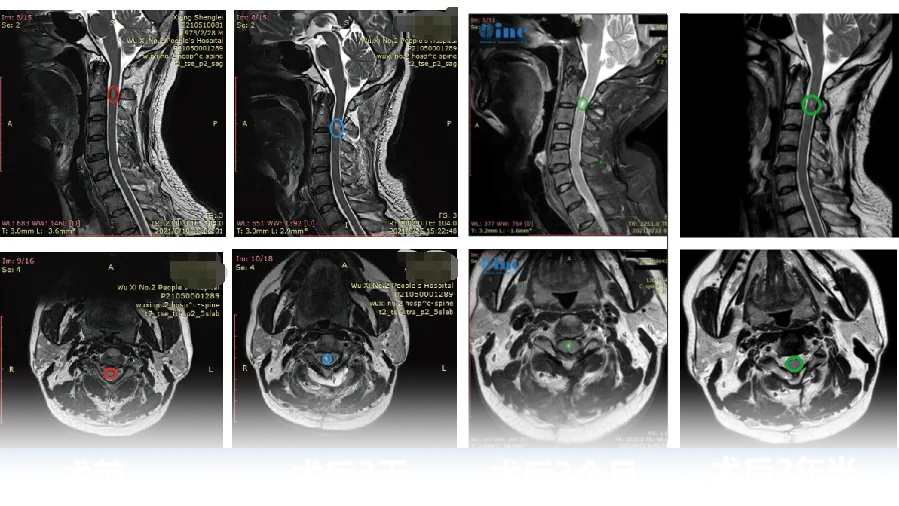

1、50岁男性——脊髓髓内室管膜瘤

病情回顾:50岁的刘先生,2年前因颈部及肩部疼痛就医检查出脊髓髓内肿瘤。由于肿瘤生长在高段颈髓内,被脊骨包围,手术暴露困难,术中脊髓稍受挤压损伤,就可能造成长期性瘫痪。很多医生都建议保守治疗。

手术结果:手术当天,在术中神经电生理监测等高医疗设备辅助下,巴教授顺利全切肿瘤,病例诊断结果为室管膜瘤。术后3天刘先生就可以下地自如行走,术前症状大多已消失,术后无长期性并发症,也无需其他辅助治疗。

2、28岁女性脊髓髓内室管膜瘤,术后3个月恢复正常生活

术前情况:28岁的潇潇6年前开始出现肩部至腰部疼痛,而两年前,潇潇肩部后侧疼痛加剧,于当地医院行磁共振检查,提示髓内占位性病变,保守治疗无效。2021年7月行增强磁共振提示C3水平占位,直径7mm。当地医院排除炎性病变。因考虑到手术风险大,未作手术治疗。2021年10月复查磁共振提示影像较前大致相仿。2022年6月磁共振提示大小约8*12*14mm。2022年10月磁共振提示8*12*19mm。

手术结果:2022年12月4日,苏州独墅湖医院,潇潇的手术顺利进行,巴教授顺利全切潇潇脊髓髓内的肿瘤,术后一天ICU查房,潇潇已经清醒,意识清楚,四肢能够正常活动。教授表示等到术后二天潇潇就可以转入普通病房,一些不舒服的症状,例如手麻等都是正常的,不属于术后并发症,后期能够恢复正常状态。